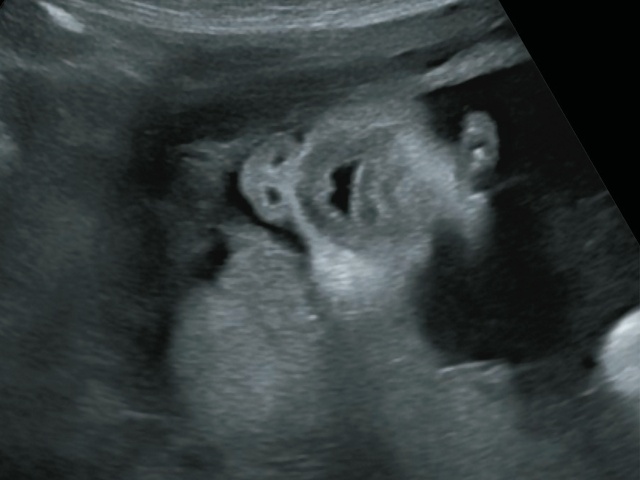

На рис. 7-12 представлена правосторонняя расщелина губы и нёба в сроке 18-19 нед беременности. Дефект имеет большие размеры. Ширина дефекта 3,8 мм.

Рис. 7. Односторонняя расщелина губы и нёба. 18-19 нед беременности.

Рис. 8. Большая правосторонняя расщелина губы и нёба (стрелка).